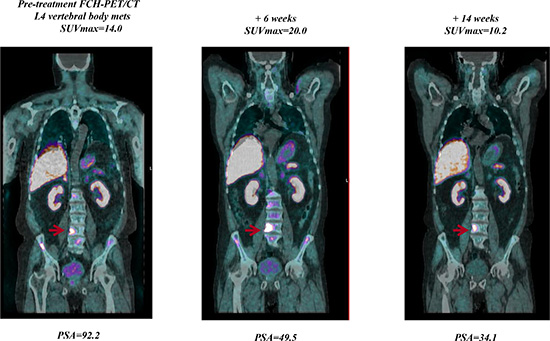

FCH-PET/CT scanning showed 3 CR, 11 PR, 6 SD, and 22 PD, but in 6 of 12 pts with initial PD at FCH-PET/CT a bone flare phenomenon was suspected due to a stable disease at 3-month CT scan associated with a progressive decline of PSA. In one case suspected for bone flare, the PET scan was not repeated due to severe intestinal infection with treatment interruption and following clinical deterioration. In another patient who had a 3-month PSA decline of 60% with SD at 3-month CT scan, the follow-up FCH-PET/CT scanning after 11 weeks confirmed PD with rapidly increasing PSA levels. Thus, overall, bone scan flare, as defined by the combination of PSA decline, initial flare, and subsequent improvement or stability in the following FCH-PET/CT scanning was observed in 4 of 42 (10%) evaluable patients and 4 of 24 (17%) responsive cases. The clinical characteristics of these 4 cases were not significantly different from the study population as a whole, median age was 71 years (range, 57 to 78), median PSA level at baseline was 15.5 ng/mL (range, 1.5–92.2), the maximal decline of PSA was 91%, 73%, 64% and 37%, respectively. The latter case who had a very low baseline PSA level of 1.5 ng/mL and PSA decline to 0.9 ng/mL (37%, lower than the threshold of 50%) was also considered to be of interest and is reported as bone flare. A PSA flare, defined as an initial PSA increment followed by a decline below the PSA baseline level, was reported in one case of bone flare, but also in another patient without bone flare. Of 4 patients with FCH-PET/CT bone flare, 3 had PD after 9, 11 and 13 months, respectively, while one is continuously progression free after 22+ months. A CR was achieved at follow-up FCH-PET/CT in 3 of the 26 (12%) evaluable patients, and was associated with undetectable PSA levels (< 0.03 ng/mL) in 1 case after 5 months on abiraterone. Of 3 patients with nodal disease only, one obtained a CR at first FCH-PET/CT and 2 a PR with a mean SUVmax reduction of 55% and 70%, respectively. Figure 1 to 3 show examples of early FCH-PET/CT effects of abiraterone, including an example of bone flare.

Figure 3: Example of a patient with a rapidly declining PSA level but a week 6 FCH-PET/CT being read as progression in bone lesions. By week 14, this progression improved, indicating that the progression seen at week 6 was due to bone flare.

An important observation that emerges from our study is the evidence of the mismatch highlighted in 4 patients between the reduction of the value of serum PSA and the detection of an increased uptake of bone lesions shown in the PET/CT after 1-2 months. This mismatch was evaluated as related to the phenomena of "bone flare", already reported in patients after treatment with abiraterone in chemotherapy-naive CRPC who had undergone bone scintigraphy, but that stands out for the first time also with FCH-PET/CT [25]. FCH-PET/CT bone flare predicted a favorable long-term outcome similar to that of FCH-PET/CT non progressive patients. The PCWG2 consensus criteria considered bone flare and included the recommendation to perform a first follow-up bone scan 12 or more weeks after the start of treatment, and furthermore defines progression in bone when a minimum of 2 new lesions are observed and confirmed on a second scan done 6 or more weeks later [5].